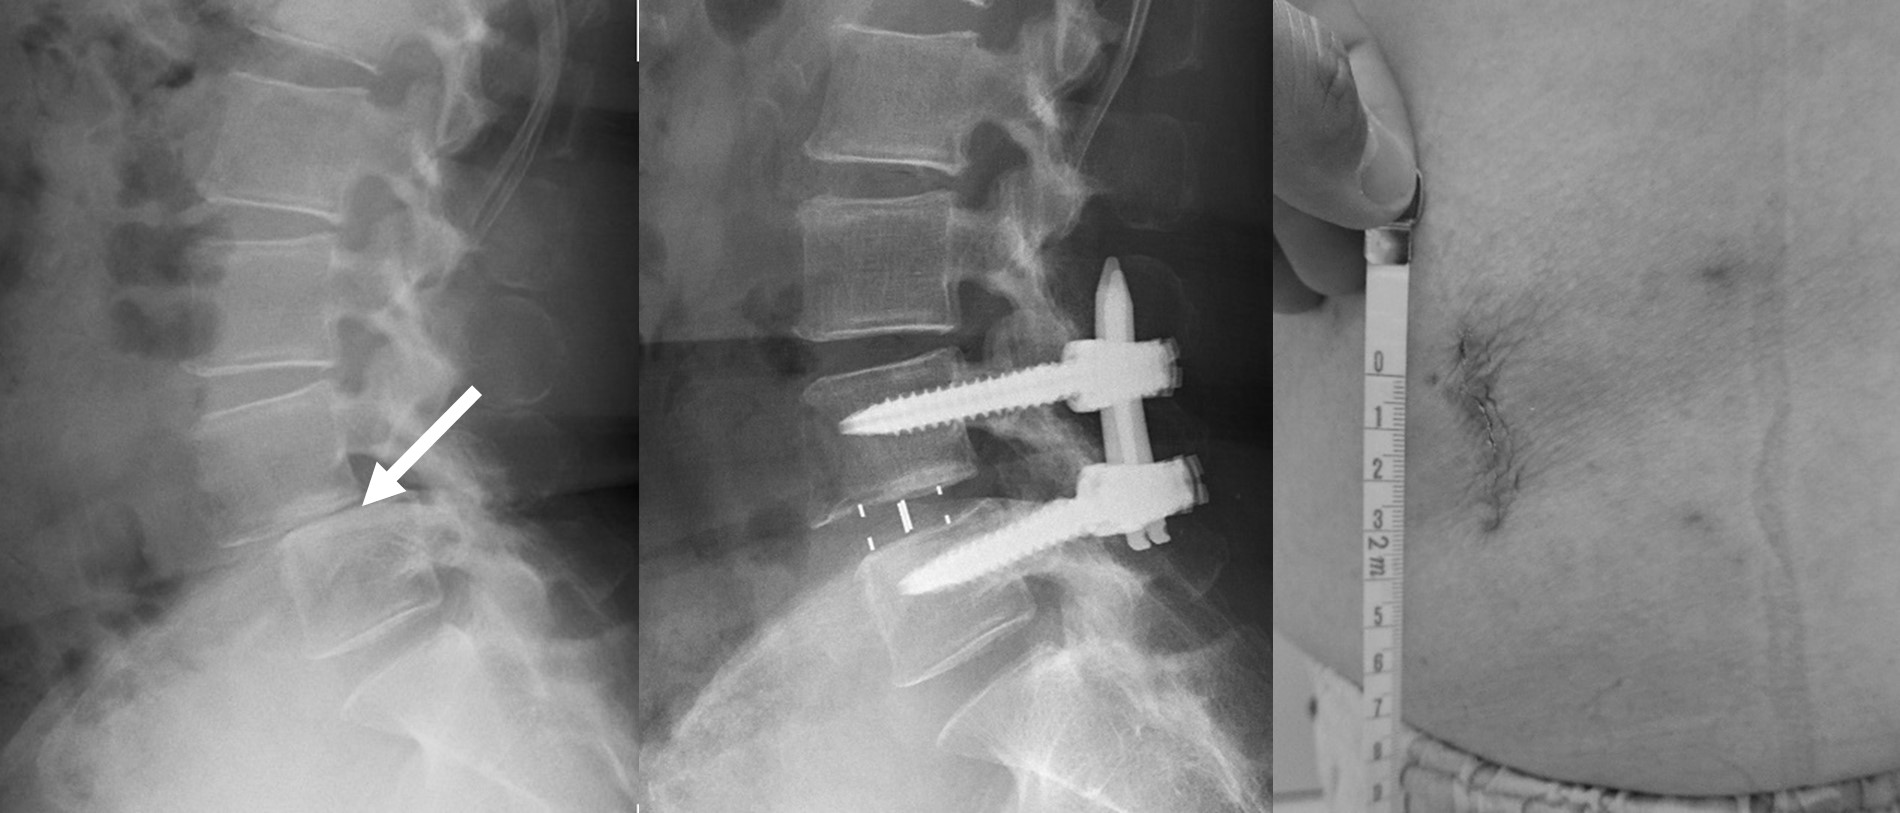

図 (左)手術前:手術前は矢印の背骨が2㎝ズレており、かつ椎間板がほぼ消失しています

(まん中)手術後:手術後はズレが矯正され、椎間板の高さも正常に戻っています。

(右)術後1ヶ月のわずか約3㎝の創の写真です。本症例では、手術前の歩行距離は50mと非常に制限されていましたが、術後3ヶ月では2kmの連続歩行が可能となりました。